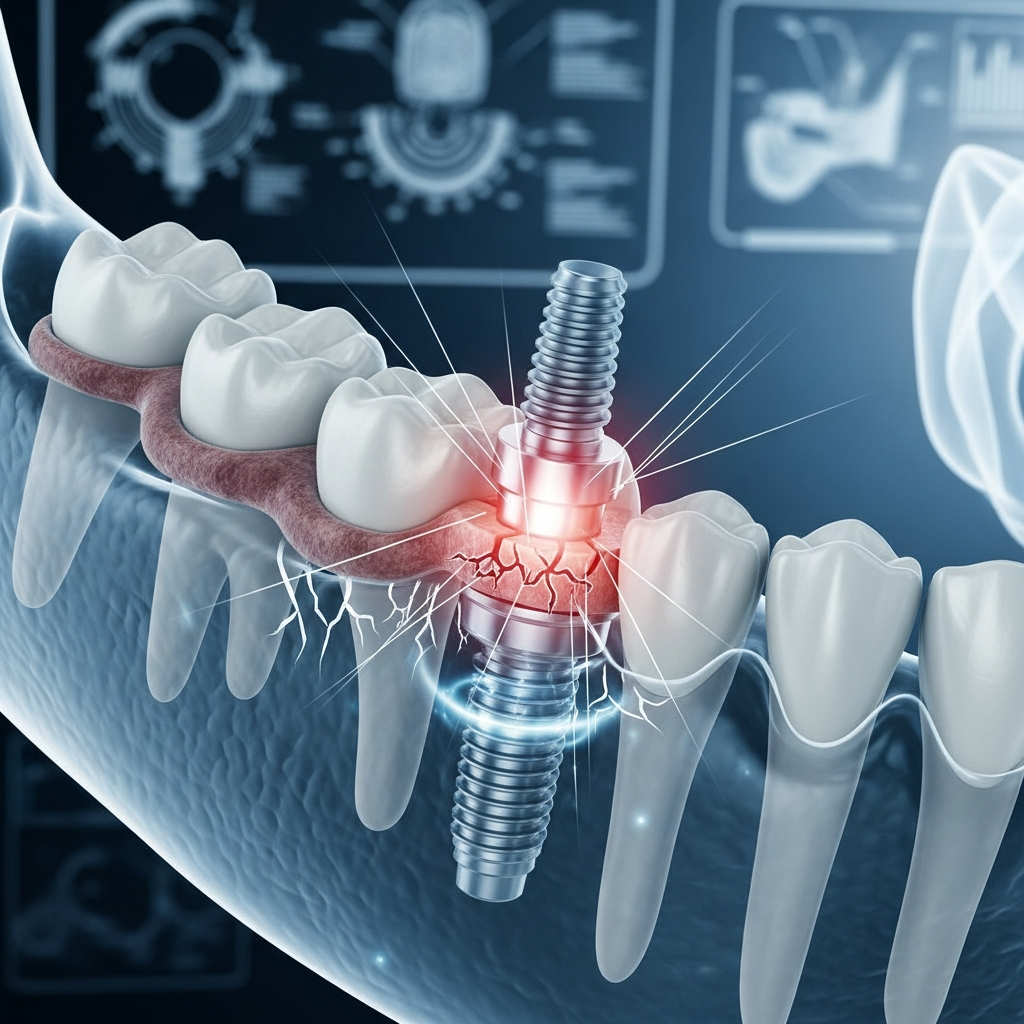

Implant Bazal Mobilizat: Semne, Cauze și Soluții Eficiente

Implantul bazal mobilizat reprezintă o complicație serioasă, caracterizată prin pierderea stabilității primare a implantului osteointegrat în osul bazal cortical dens. Această mobilitate, diferită de cea a implantului recent inserat, indică eșecul osteointegrării și necesită o intervenție promptă. Cauzele frecvente, conform literaturii medicale recente (2025–2026), includ supraîncărcarea ocluzală precoce, calitatea osului insuficientă sau infecții peri-implantare. Diagnosticul se bazează pe examene clinice și imagistice specifice, iar abordarea terapeutică variază de la decontaminarea și re-osteointegrarea în cazuri minore până la explantarea și reconstrucția osoasă în situații avansate.